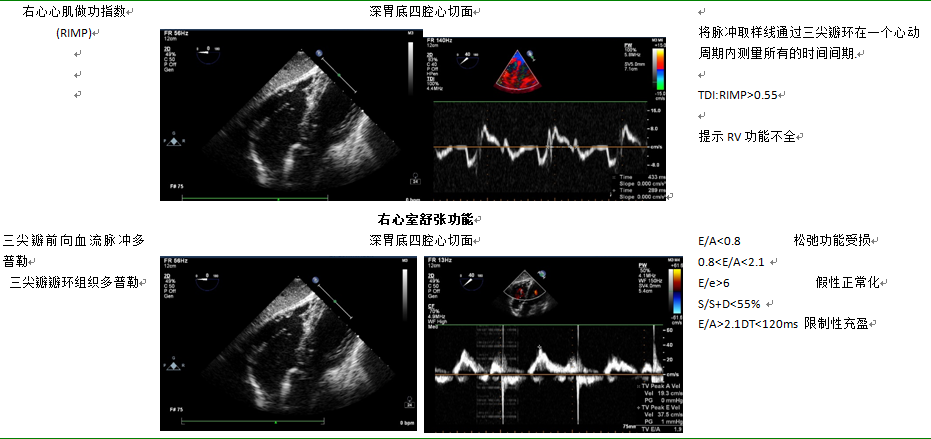

10.3.3右心室功能如表7所示

表7  右心室功能评估

12.2.2右心衰食管中段四腔心、右心室流入-流出道切面及胃底心室短轴切面评估。

右心室腔扩张,右室游离壁波幅减低,三尖前瓣瓣环运动减低。常见于右室心肌缺血,急性肺动脉高压,急性较大的肺动脉栓塞。肺栓塞,右室心梗,肺动脉高压,大房缺,二尖瓣狭窄晚期,三尖瓣重度反流,肺静脉异位引流(图14)。这类心脏右心室舒张末压升高,如遇到左房压急性升高的因素(急性左心衰、突发心房颤动、二尖瓣急性关闭不全),发生心跳骤停的风险较高。